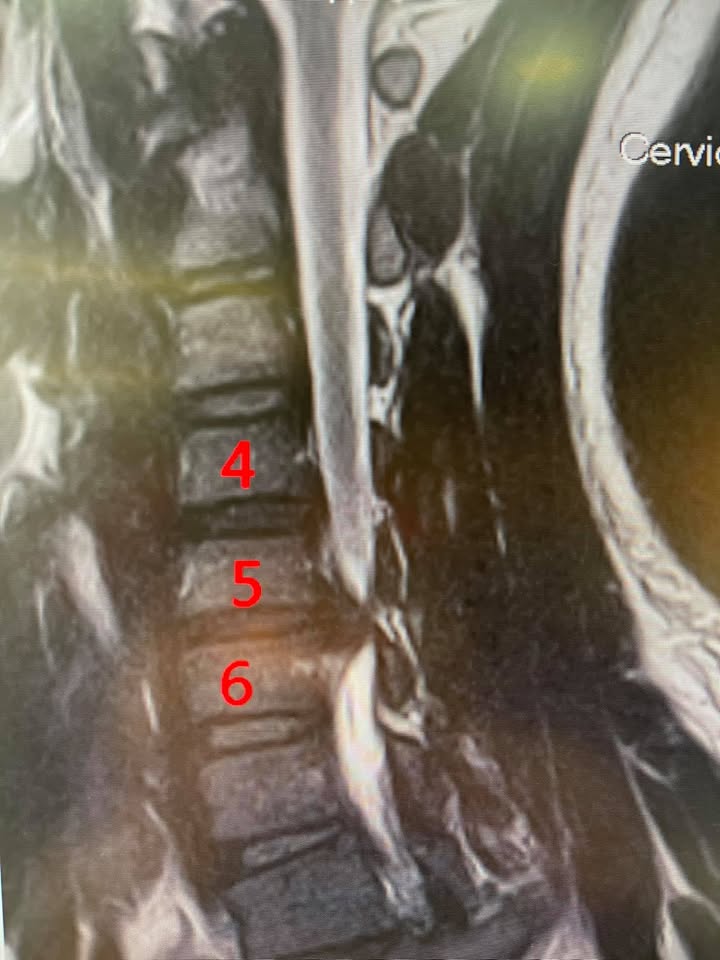

Cervical Spine Treatment Cases 頸椎治療案例 頸椎壓迫竟導致自律神經失調?耳鳴、心悸、暴瘦全因筋膜失衡! 2021.02.18 頸椎壓迫神經根導致工作受限?非手術微創療法改善關鍵公開 2021.02.17 頸椎脊髓壓迫五大症狀公開!你也有雙腳沉重、手腳麻電感嗎? 2021.01.15 長期頭痛吃藥沒效?小心你可能是「頸源性頭痛」患者 2021.01.07 #感謝新北市蘆洲區楊先生熱情見證 #頸椎病變引起肩膀痠痛無法睡眠 #曾經大痛到想立刻... 2020.12.31 #感謝新北三重劉小姐熱情見證 #神經根型頸椎病經典案例 #曾經手麻痛到無法騎摩托車 #... 2020.12.25 #遠從台東縣的熱情見證 #五個多小時的車程三百多公里很辛苦 #疼痛超過兩年打過頸椎三... 2020.12.24 #頸椎酸痛到無法睡覺是怎們回事 #醫學中心證實頸椎間盤突出 #神外醫師建議開刀但患者... 2020.12.19 #頸椎曲線弧度非常重要 #頸椎嚴重壓迫有可能逆轉嗎 #肩膀疼痛到不行合併走路都無力 #... 2020.12.09 頸椎退化壓迫神經根怎麼辦?大直林小姐四週見效的中醫微創療法 2020.12.08 #特殊案例長年過敏性鼻炎 #起因居然是頸椎交感神經筋膜壓迫 #打開椎動脈循環🔄找到解... 2020.12.05 #恭喜新店陳小姐頸椎療程畢業 #神經根型卡壓醫案 #頸椎整合中醫微創療法逆轉勝 #告別... 2020.11.24 #特殊案例頸椎手術後又再度突出案例 #感謝台中劉大哥熱情見證 #親自手捏醫師娃娃公仔... 2020.11.18 #頸椎病居然會導致手快速萎縮 #脊髓型頸椎病案例 #感謝高雄王大哥熱情見證 #頸椎整合... 2020.11.13 #神經根型頸椎病讓人痛到無法入眠 #感謝新店陳小姐熱情見證 #患者的疼痛日誌讓人感動 ... 2020.11.11 ← 上一頁 3 4 5 6 7 下一頁 →